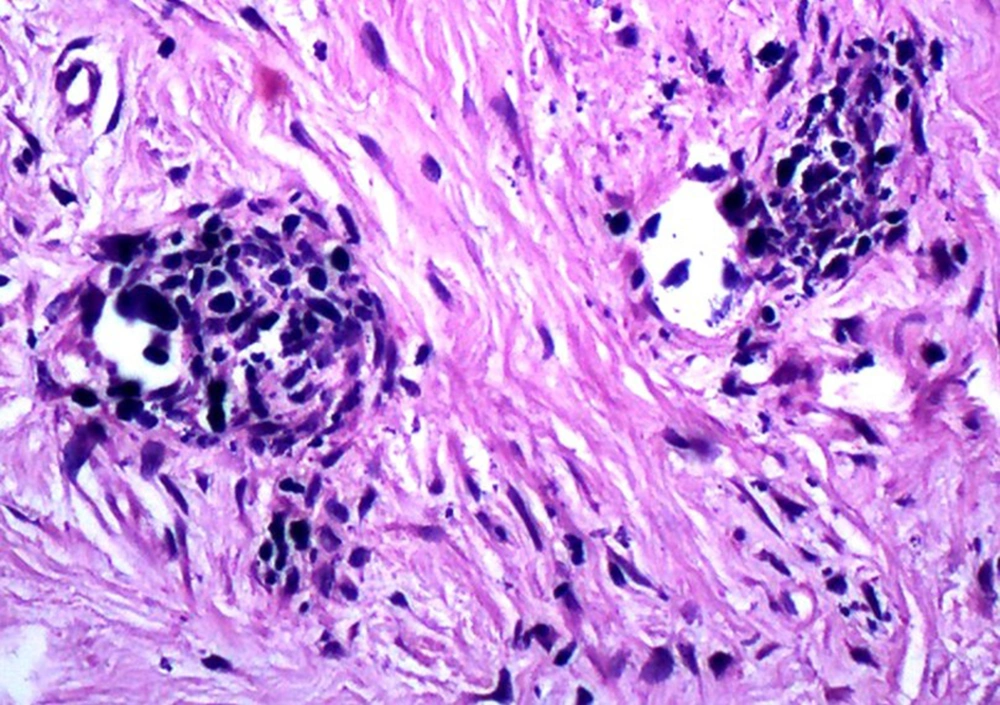

A 13-year-old boy with the chief complaint of multiple unerupted teeth was referred to department of Oral and Maxillofacial Surgery of Ahvaz University of Medical Sciences in May 2013. The panoramic radiograph revealed 15 unerupted teeth (8 in mandible and 7 in maxilla) with large pericoronal radiolucent zone (enlarged follicles) delineated by a well-defined sclerotic borders (Figure 1). Tooth abnormalities such as amelogenesis imperfecta were not seen. Medical and familial history was unremarkable and his siblings had normal dentition. The patient had normal intelligence. He did not have other signs and symptoms like cleidocranial dysplasia, Gardner syndrome, or mucopolysaccharidosis (three syndromes with tendency to multiple impactions). The incisional biopsy was performed with provisional diagnosis of Gorlin syndrome (multiple keratocystic odontogenic tumors). Microscopic examination revealed a dense and cellular fibrous connective tissue with numerous deposits of calcifications. Collagen fibers were arranged in whorled structures. Cords and islands of odontogenic epithelium with numerous clear cells were surrounded by these deposits. Calcifications were found in the whorled areas. There were many small circular droplets of basophilic calcified material resembling cementum. Most of the droplets were homogenous (up to 95%), but some revealed concentric layering similar to Liesegang rings of Pindborg tumor. The diagnosis was atypical follicles with odontogenic fibroma-like changes (WHO type) or hyperplastic calcified dental follicles (Figures 2- 4). Then, the excisional biopsy was performed for mandibular lesions. Grossly, the specimen consisted of multiple pieces of creamy brown soft tissues surrounding the crown of multiple extracted teeth totally measuring 5 × 5 × 1 cm. The lesions showed fine surface nodularities and produced a distinct grating sound during sectioning (Figure 5). The initial diagnosis has been confirmed. Additional surgical procedure must be performed for maxillary lesion in future.